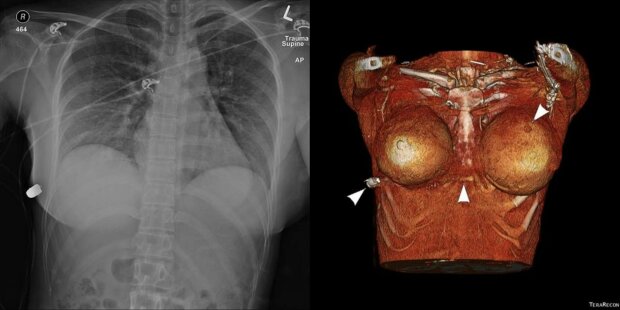

30-річна мешканка Канади розповіла, що, коли вона йшла по вулиці, раптово відчула в тілі печіння і біль. А потім побачила кров. Дівчину доставили в клініку в місті Міссіссога, де хірурги витягли з її грудей кулю, яку відправили на експертизу.

Незважаючи на те що куля потрапила в область грудної клітини зліва, дівчина залишилася жива і відбулася лише зламаним ребром. Медики припускають, що канадку врятували від смерті силіконові груди, так як імплантат змінив траєкторію кулі, яка летіла в серце. Як пізніше з'ясувалося, під час нападу постраждав і другий імплантат, так що дівчині довелося розпрощатися з пишним бюстом. Дивовижний випадок був описаний на сайті Sage journal.